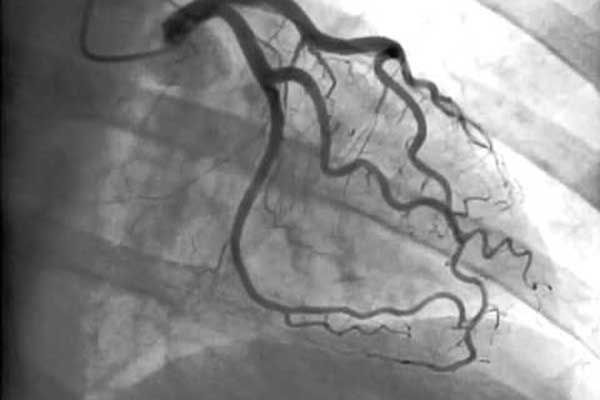

Cateterismo cardiaco: Estudio que permite visualizar las arterias del corazón y detectar obstrucciones.

Angioplastia coronaria y colocación de stent: Procedimientos para abrir arterias bloqueadas y restaurar el flujo sanguíneo.

Cateterismo periférico: Estudio de arterias en otras zonas como carótidas, renales, aorta y extremidades, útil para detectar problemas de circulación.